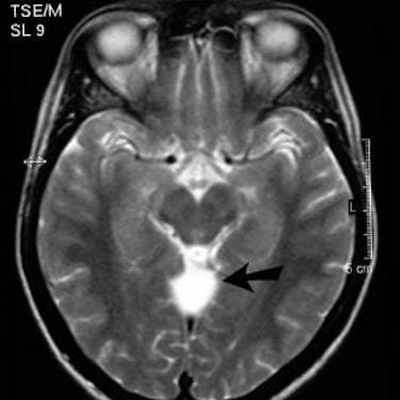

43. МР картина мальформации Dandy-Walker.

МР картина мальформации DandyWalker.

Кистозно расширенный 4-ый желудочек,

заполняющий большую часть объема ЗЧЯ.

Червь не определяется или резко

гипопластичен.

Полушария мозжечка раздвинуты и

уменьшены в объеме.

Мозжечковый намет расположен высоко.

3-и и боковые желудочки гидроцефальны.